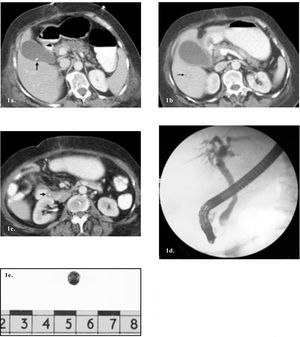

A contrast-enhanced CT demonstrated an incarcerated right colon within a post-operative ventral hernia. A single stone in the gallbladder was also seen (Figure 1a).

Contrast enhanced CT demonstrating a small calcified gallstone (arrow) within the gallbladder. 1b+c. Contrast enhanced CT two weeks later. b. A dilated gallbladder with thickened wall, absence of stone, and intrahepatic bile duct dilatation (arrow). 1c. The migrated gallstone (arrow) is seen in the distal CBD. 1d. ERCP demonstrating a filling defect in the distal CBD. 1e. The extracted gallstone.

A repeat abdominal CT demonstrated a dilated, thickened walled gallbladder, dilatation of intra and extrahepatic bile ducts and the previously demonstrated gallbladder stone was now located within the distal choledochus (Figures 1b+c).

Antibiotics were started and the patient underwent an emergent ERCP demonstrating the migrated stone within the distal choledochus (Figure 1d). A sphincterotomy was performed and a single black pigment stone (Figure 1e) was successfully extracted.